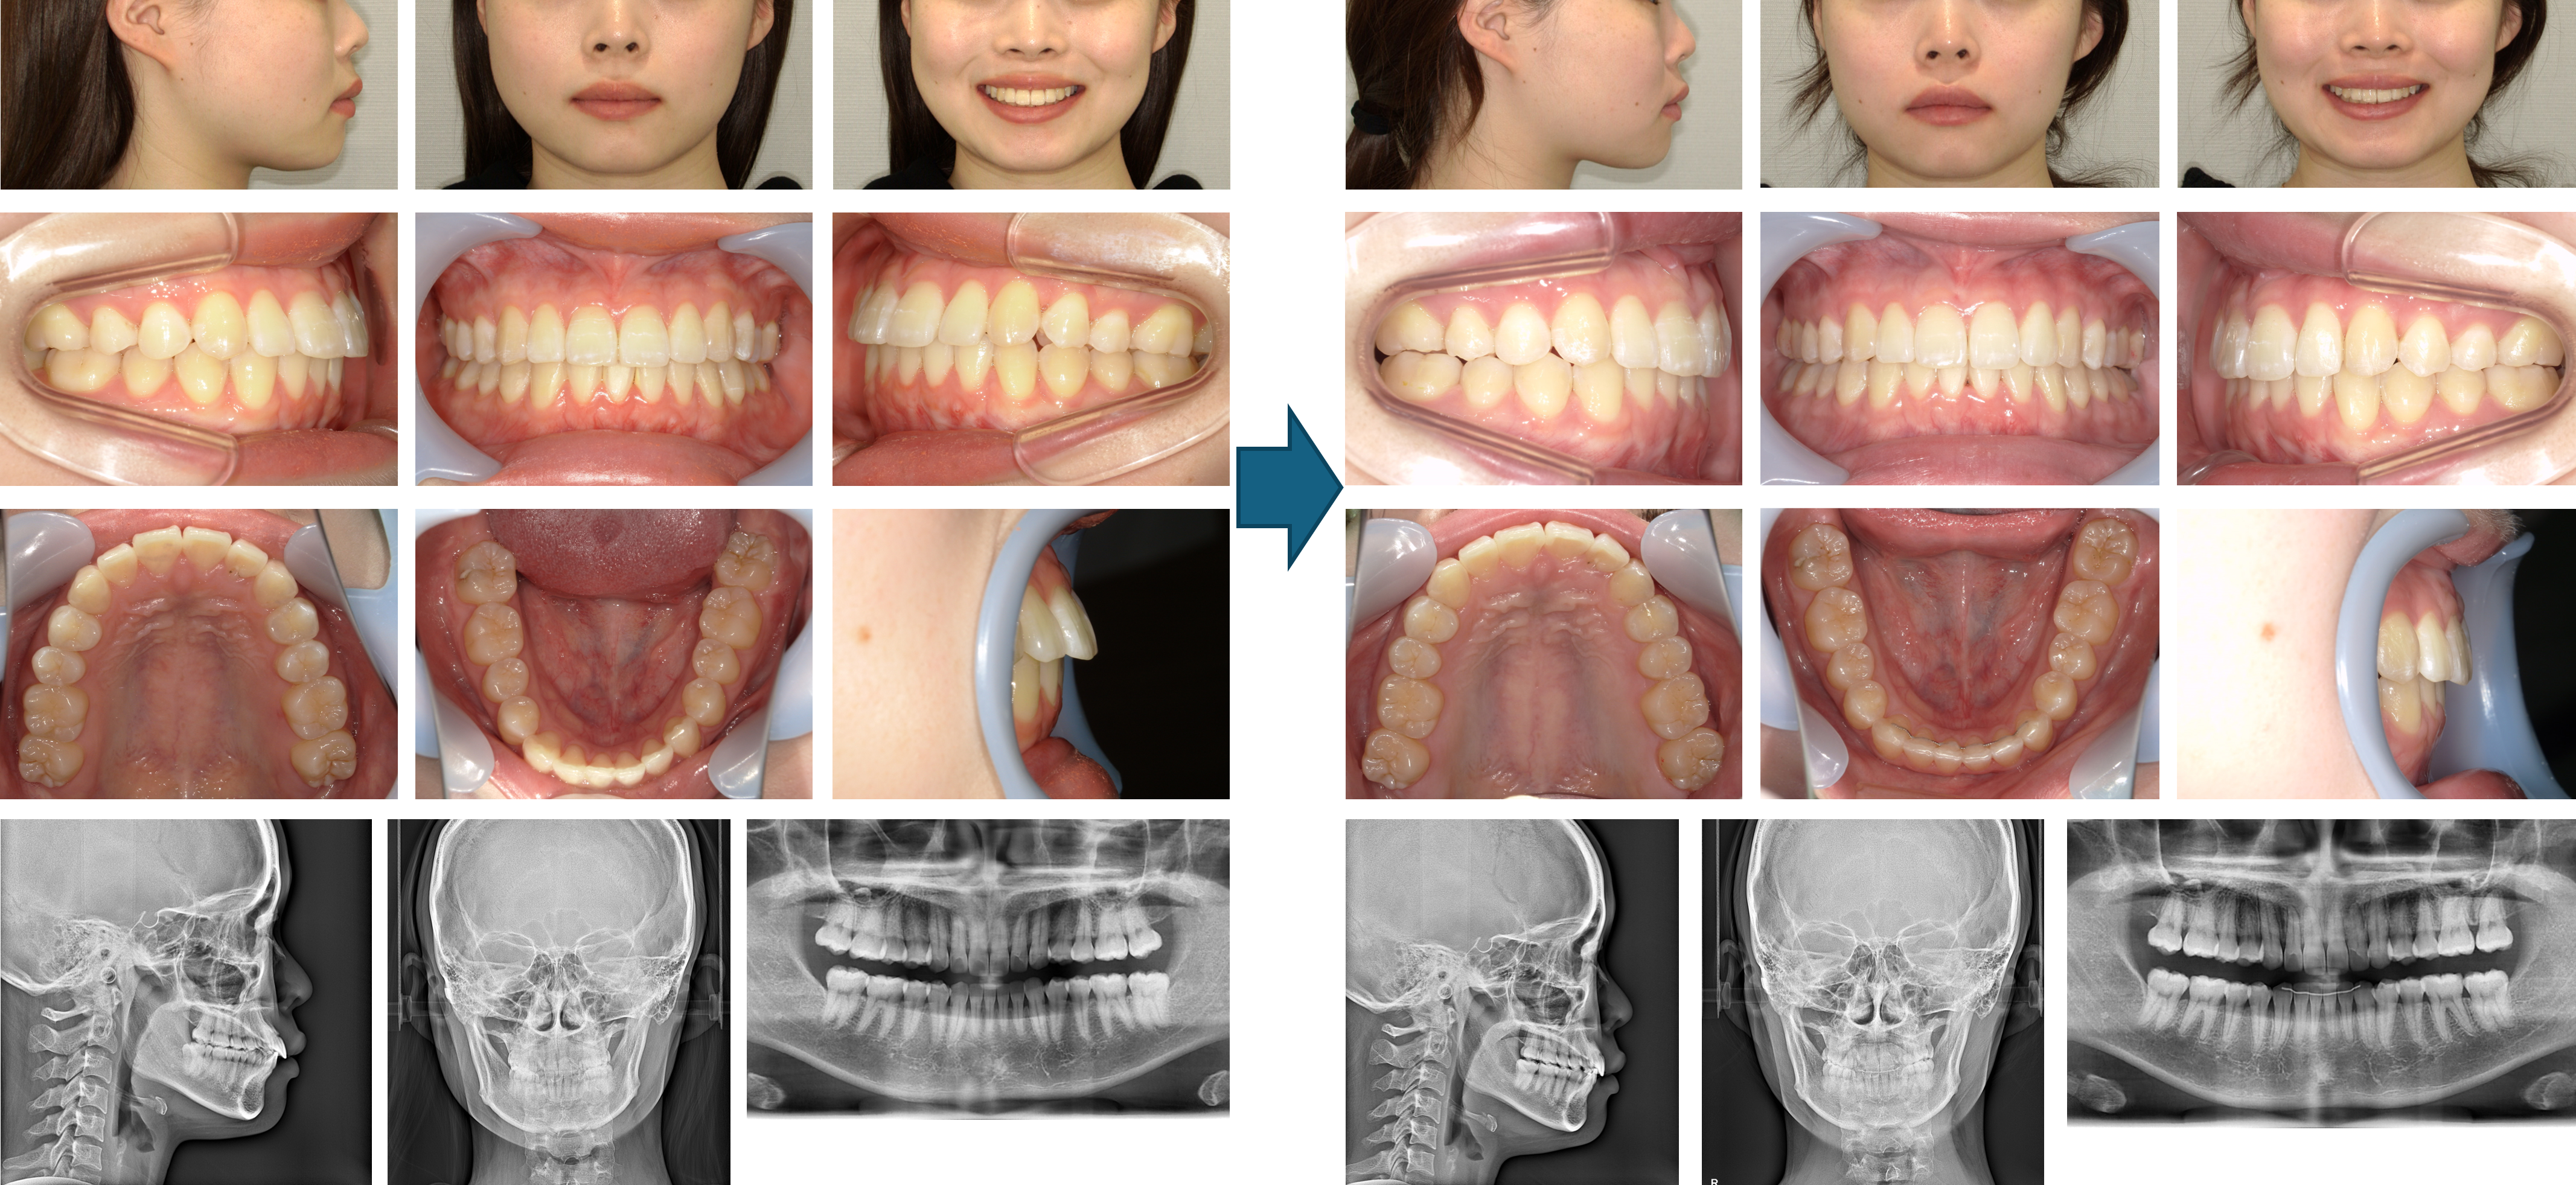

【治療例】初診時年齢:22歳10か月 / 性別:女性 / 主訴:出っ歯、物が噛み切れない

主訴: 出っ歯、物が噛み切れない

診断名: 開咬

使用した主な装置: マウスピース型(アライナー型)矯正装置(インビザライン®)、IPR

抜歯/非抜歯および抜歯部位: 非抜歯

※上記価格は税込価格です。消費税は10%で表示しております。

※こちらの症例は2019年12月から2022年9月に行った矯正治療です(現在も経過観察中)

治療期間:2年9か月

来院回数:43回

リスクの副作用:歯の移動や抜歯による違和感や疼痛、口内炎、歯肉退縮、歯根吸収が生じることがある